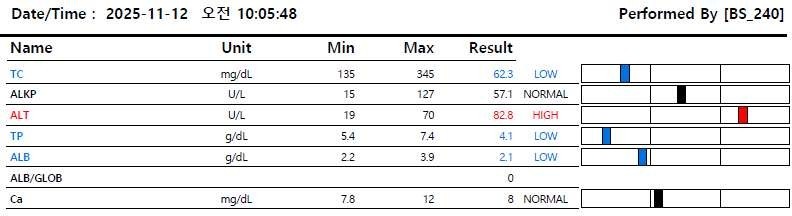

[혈액 검사]